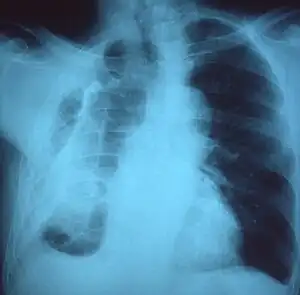

A fibrothorax can typically be diagnosed by taking an appropriate medical history in combination with the use of appropriate imaging techniques such as a plain chest X-ray or CT scan.[1] These imaging techniques can detect fibrothorax and pleural thickening that surround the lungs.[11] The presence of a thickened peel with or without calcification are common features of fibrothorax when imaged.[1] CT scans can more readily differentiate whether pleural thickening is due to extra fat deposition or true pleural thickening than X-rays.[1]

If a fibrothorax is severe, the thickening may restrict the lung on the affected side causing a loss of lung volume.[11] Additionally, the mediastinum may be physically shifted toward the affected side.[1] A reduction in the size of one side of the chest (hemithorax) on an X-ray or CT scan of the chest suggests chronic scarring.[9] Signs of the underlying disease causing the fibrothorax are also occasionally seen on the X-ray.[9] A CT scan may show features similar to those seen on a plain X-ray.[11] Lung function testing typically demonstrates findings consistent with restrictive lung disease.[9]

Chest radiograph displaying inhomogeneous opacification of the left half of the chest that is fibrothorax -

Chest X-ray showing bilateral fibrosis and pleural thickening in infection with non-tuberculosis mycobacteria.